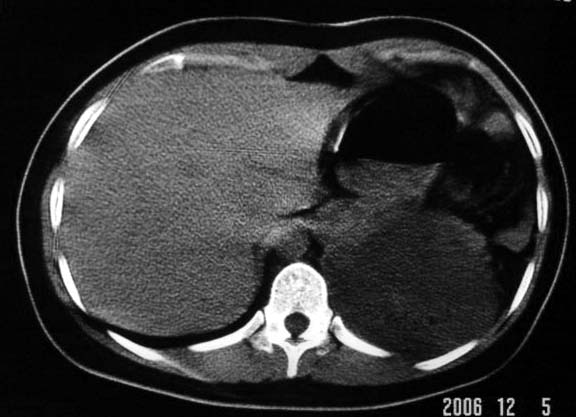

标题: CT5517:女性、24岁,反复胸痛、气促不能平卧半月。 [打印本页]

标题: CT5517:女性、24岁,反复胸痛、气促不能平卧半月。

左侧气液腔与胃腔影相连,考虑膈疝。钡餐检查有助于诊断。

我看这是膈疝,在纵隔窗第六\\七幅图像上可见胃粘膜影,再者可见两个腔影,这在液气胸是不会有的.

综合分析考虑:1左侧包裹性液气胸。2左侧胸膜肥厚。3左肺膨胀不全

液气胸 怎么会有2 个大腔?

左肺发育不良、支气管囊肿 应该纵隔左移的多吧

还是个膈疝